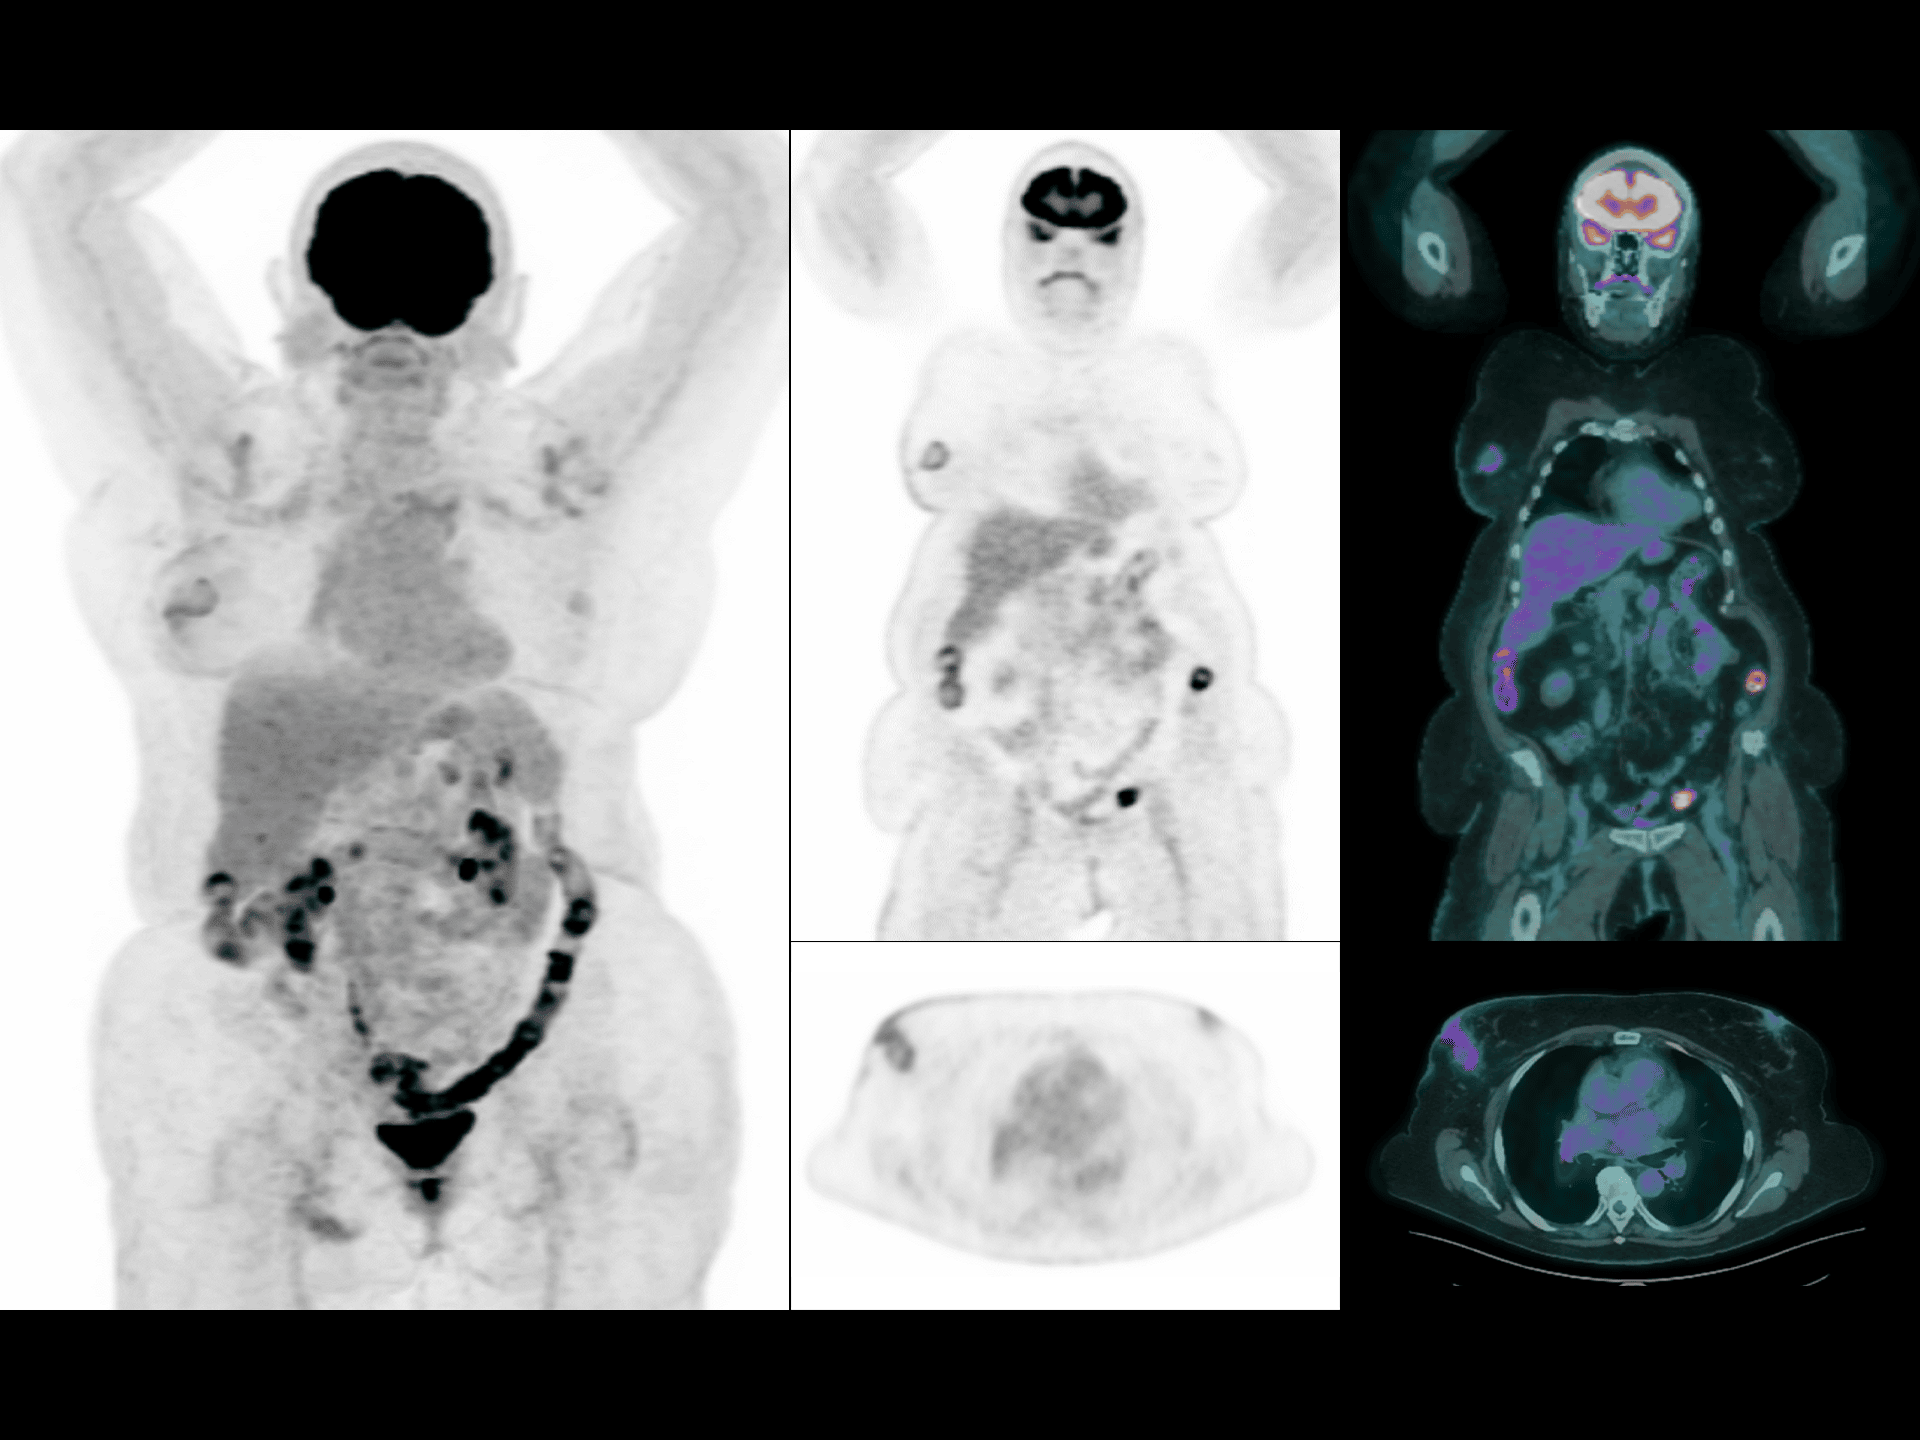

Imagistică total-body în 10 minute, cu doză redusă

Scanări PET/CT eficiente, cu expunere minimă pentru pacient.

Imagistică whole-body rapidă, în doar 2 minute

Performanță clinică de top, cu timp redus de examinare.

Imagistică low-dose pentru pacienți cu IMC ridicat

Calitate înaltă a imaginii, chiar și la pacienți cu indice de masă corporală mare.